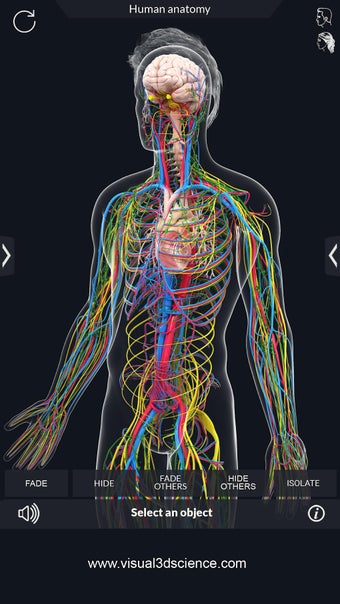

La anatomía humana es una aplicación educativa médica que te permite explorar el cuerpo humano desde todos los ángulos. Ofrece una mirada detallada a la anatomía de los diferentes sistemas, así como a los órganos y sus funciones. Es una referencia perfecta para estudiantes y profesores de medicina.

Puedes seleccionar cada parte del cuerpo por separado para ver su nombre o leer información relacionada. Puedes ocultar y mostrar cada parte del cuerpo, así como rotar 360° alrededor de un modelo 3D altamente realista. Puedes dibujar en la pantalla o compartir capturas de pantalla con tus amigos. Puedes encontrar la definición de cada parte del cuerpo y su anatomía.